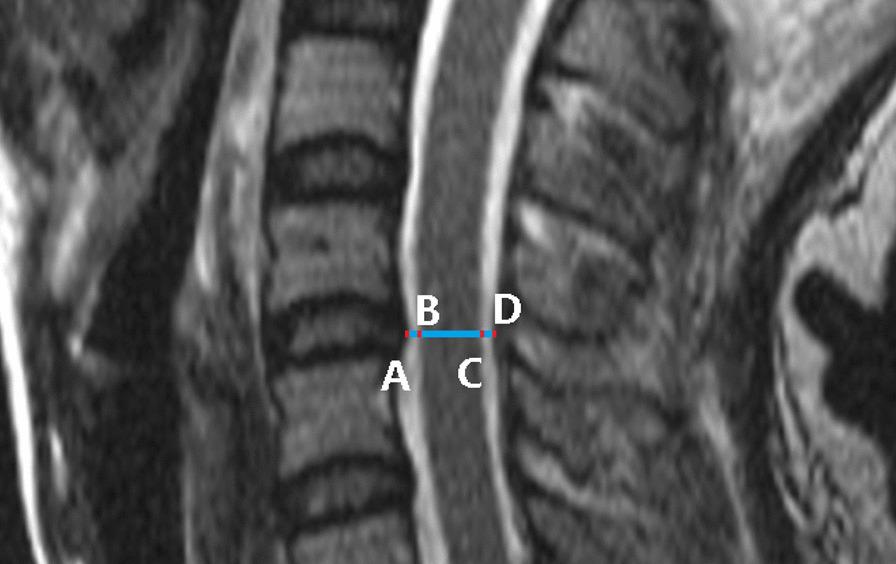

Using median sagittal T2-weighted images for 16 patients with cervical spinal cord injury without fracture and dislocation who underwent cervical kinematic MRI, the anterior space available for the cord, spinal cord diameter, posterior space available for the cord from C2/3 to C7/T1, and Muhle's grade were determined. The spinal canal diameter was calculated by adding the anterior space available for the cord, spinal cord diameter, and posterior space available for the cord.

对 16 例无骨折脱位型颈脊髓损伤患者行颈椎 K-MRI 检查,采用正中矢状面 T2 加权像测量 C2/3 至 C7/T1 颈髓前方有效间隙(available for the cord,AC)、脊髓直径、脊髓后方有效间隙(posterior space available for the cord,PSC)及 Muhle 分级,椎管直径为 AC、脊髓直径和 PSC 之和。